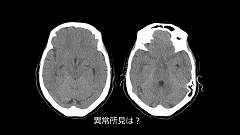

第5回は、頭部画像の基礎編です。頭部CTの読影は、初心者にとってなかなか難しいものですよね。まずは頻度の高い脳血管障害の読影をしっかりマスターしましょう。講義では、脳梗塞と脳出血の鑑別方法や、early CT signといった見逃し厳禁の重要所見を整理。さらにMRIの各撮像法の基本と、脳出血の経時的なMRI信号の変化までレクチャーします。

今回は、頭部画像の実践編として、重要所見が潜む症例を複数紹介します。典型的なくも膜下出血であれば見落としは少ないですが、注意すべきは出血量の少ない“微細な”くも膜下出血。どの部位を念入りに確認したらよいか、具体的にお伝えします。続いて、頭部外傷で見逃されやすい頭蓋骨骨折の読影ポイントを提示。最後に、静脈洞血栓症の症例を通じて、CT、MRIを用いた多角的な診断のヒントを伝授します。